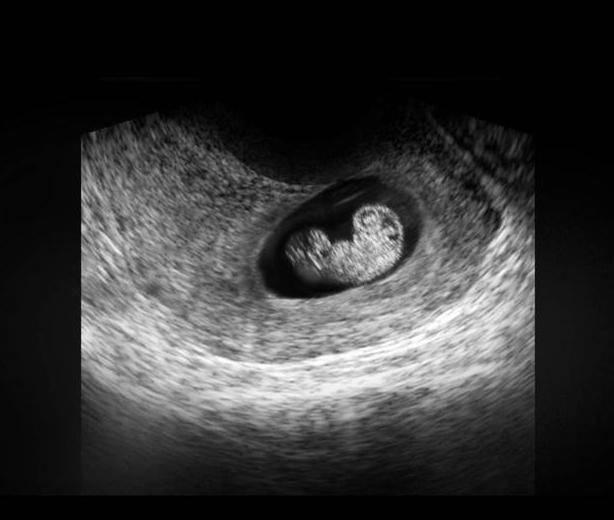

在上图可见是个双胎妊娠,胎儿具有一个很大的头,和身材很不对称,是不是跟出生后的胎宝宝有点像了?其实此时的头部比例更悬殊,宝宝的额面部器官发育很明显,心脏也开始了跳动,出现了胎心,此时做B超,可见胎心胎芽。